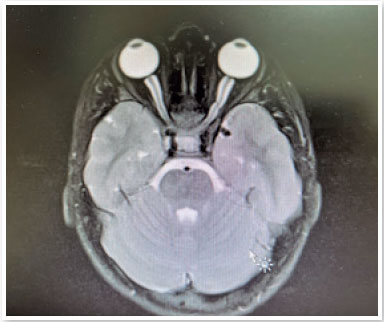

Based on these findings, an MRI examination was requested, which revealed a thickening of both optic nerves in the chiasm region (Figure 2). Thus, an optic nerve glioma hypothesis was confirmed and the child was referred for chemotherapy treatment.

Figure 2. Chiasmal thickening.

After 5 years, the child underwent significant tumor reduction (Figure 3), maintaining nystagmus (Video 2) and presenting with a 20/25 visual acuity in both eyes. In the fundus picture, a temporal pallor of the optic nerve can be observed (Figure 4).

Figure 3. MRI revealing tumor reduction.